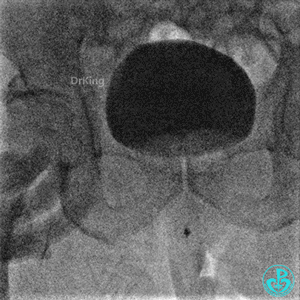

撤回逆向导丝及微导管造影,钝缘支远端侧支造影剂渗漏,局部造影剂滞留范围不断扩大。

明胶在血管怎么降解并发症丨前降支CTO同侧逆向开通时侧支血管破裂,弹簧圈联合明胶海绵封堵_https://www.jmylbn.com_新闻资讯_第31张

明胶在血管怎么降解并发症丨前降支CTO同侧逆向开通时侧支血管破裂,弹簧圈联合明胶海绵封堵_https://www.jmylbn.com_新闻资讯_第32张

前降支末梢经微导管释放3.0×2.5mm弹簧圈封堵破口。